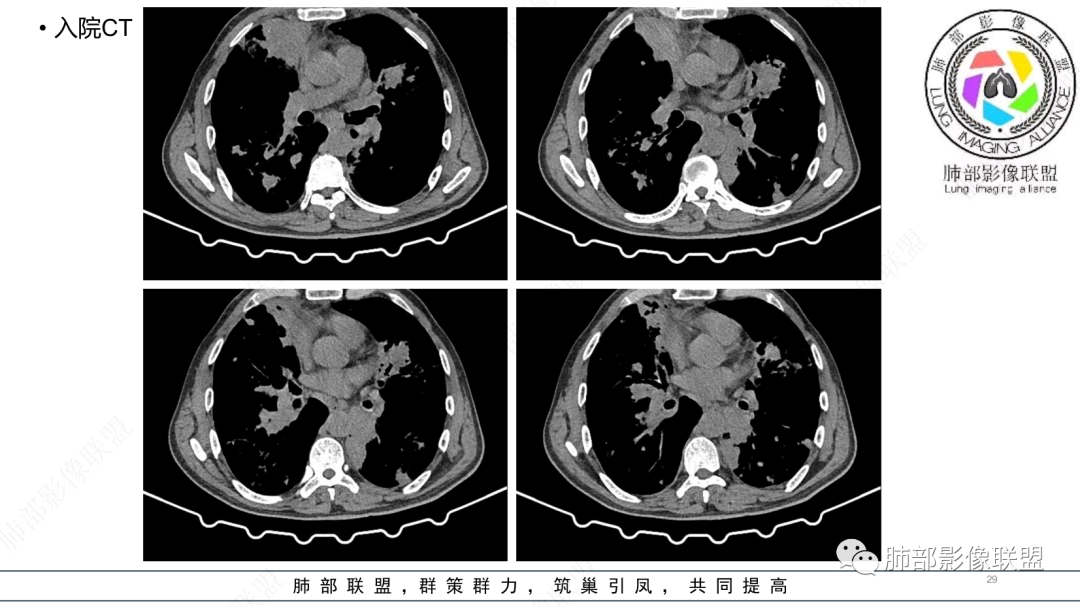

中老年男性,发病一周,发热,炎症指标明显增高,双肺支气管扩张基础,双肺可见多发结节、斑片状、团块状密度增高,边缘尚清。病灶分布与支气管关系密切,考虑支扩合并感染,铜绿,NTM、奴卡、曲霉等,环卫工人,可能接触腐败物较多,考虑曲霉可能大,鉴别奴卡。

56岁,工作性质:环卫工人。主诉:咳、痰、喘、发病一周。急性起病(或者慢病+AE),呼吸道感染症状。化验指标白细胞、中性、CRP明显升高。影像学显示多灶性,有柱状支扩,囊状支扩等结构肺病,责任细菌主要考虑铜绿假单胞菌,不排除合并其他细菌以阴杆为主;存在树芽影,发热,炎症沿支气管束分布,是否合并TB?真菌?;树芽伴发热支原体感染也要需要考虑进去;全肺多灶性炎症,部分病灶周围有晕,右上叶疑似反晕,内部疑似有丝,右下肺考虑存在粘液栓,加之环卫工工作性质,考虑霉菌,主要考虑曲霉。

两肺支扩,两肺沿支气管分布多发结节、树芽及团块,边缘模糊,部分支气管管壁增厚,考虑气道侵袭性曲霉菌,鉴别铜绿、奴卡、结核。

支气管壁增厚,晕征明显,病灶沿着支气管纵向分布,结合患者职业,考虑气道侵袭性曲霉。

多发结节,部分结节边缘清楚,部分边缘模糊,支扩合并肉芽肿性炎,奴卡菌与曲霉之间选择。

影像改变为支扩伴气道来源感染,部分实变性伴有小脓肿及钙化,结合PCT及白细胞、中性粒明显增高,符合细菌感染,首先考虑奴卡,绿脓次之,因为临床有喘息、影像实变性有钙化,加上环卫工这一职业史,需要鉴别曲霉或奴卡合并曲霉。